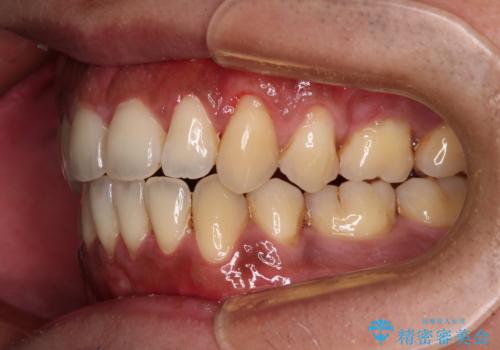

- 上下前歯の隙間と口元の出っ張った感じを気にして来院された患者様です。

上下の隙間は舌突出癖によるもので、またその癖により前歯が前方に出ている状態でした。

口元の出っ張りを改善するため、上下左右第一小臼歯4本を抜去し、ワイヤー装置にて矯正治療を行うこととしました。